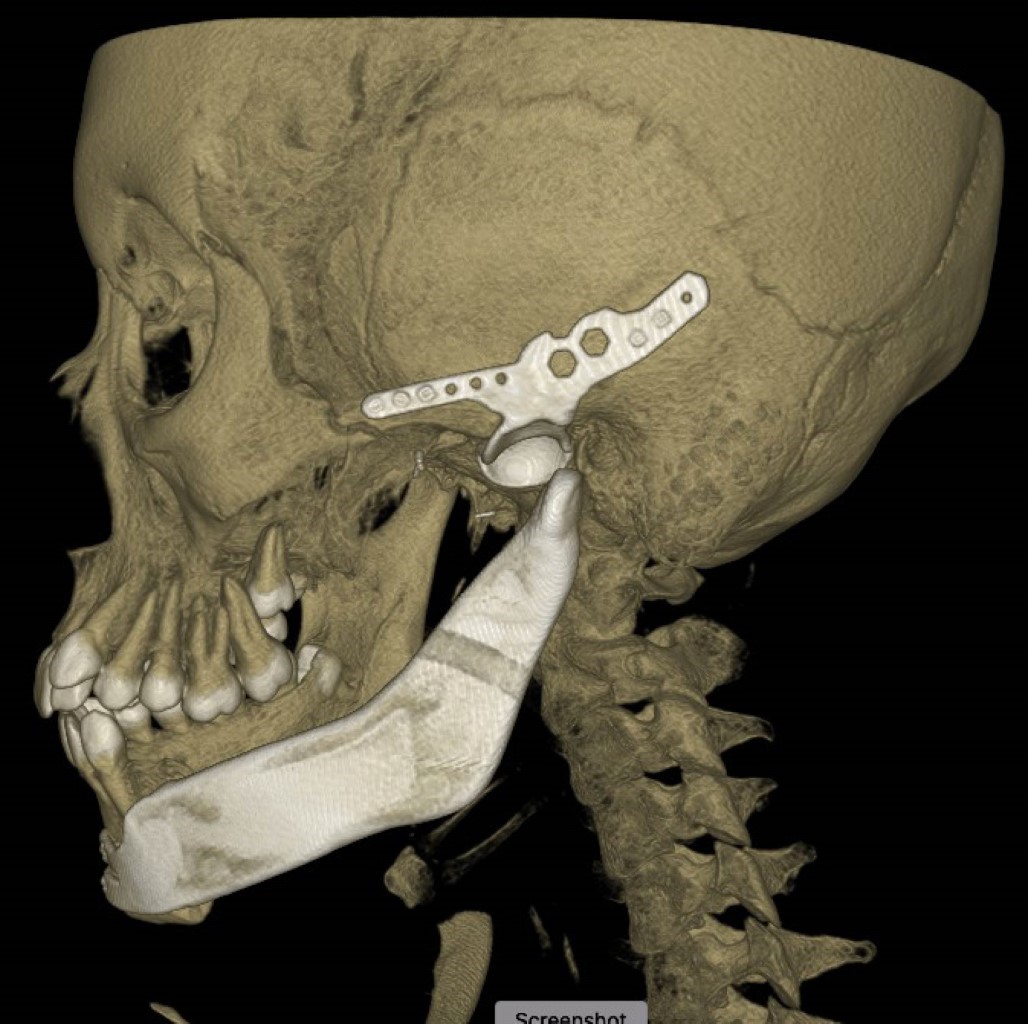

La planificación virtual permitió diseñar guías de corte para realizar la excisión de la lesión mediante mandibulectomía segmentaria dejando un margen de 1.5 cm (Figuras 7 y 8). Simultáneamente, se realizó la reconstrucción con prótesis personalizada, incluyendo la rama mandibular, cóndilo y cavidad glenoidea. La fijación se logró con tornillos del sistema 2.4 y 2.0.

Durante el procedimiento quirúrgico, posterior a la fijación de la parte anterior de la prótesis con el cuerpo mandibular remanente, se observó una discrepancia en el ajuste del cóndilo de la placa mandibular con la cavidad glenoidea, quedando éste en una posición posterior al centro de la cavidad metálica.

Después del procedimiento quirúrgico, se solicitó un estudio tomográfico control, observando el retiro completo de la lesión; sin embargo, el cóndilo de la prótesis mandibular se encontraba posterior a la cavidad glenoidea como se presentó durante el procedimiento quirúrgico (Figuras 10 y 11). A pesar de una discrepancia en la posición del cóndilo, la paciente presentó adecuada evolución funcional, sin recurrencia a ocho meses del procedimiento presentando movimientos de apertura y cierre mandibular adecuados y oclusión estable.

La reconstrucción mandibular mediante prótesis personalizada constituye una opción terapéutica moderna y efectiva, especialmente en casos complejos que involucran la articulación temporomandibular. La planeación virtual ha demostrado ser una herramienta clave para el diseño preciso de prótesis, mejorando los resultados quirúrgicos y funcionales. No obstante, persisten desafíos relacionados con la biomecánica y la adaptación de la prótesis, como se evidenció en la discrepancia del ajuste entre el cóndilo y la cavidad glenoidea en este caso.10,11,16

Las dificultades con el ajuste de las prótesis presentadas durante el procedimiento quirúrgico se deben posiblemente a la diferencia de densidades entre la parte anterior de la prótesis y el cuerpo mandibular; sin embargo, no hubo necesidad de realizar fijación intermaxilar y la paciente ha presentado adecuada oclusión y movimientos de apertura y cierre mandibular conservados en los siguientes ocho meses. Este tipo de complicaciones resalta la necesidad de un seguimiento cercano y multidisciplinario para garantizar una recuperación funcional y estética óptima.16

Figura 7

Figura 8

Figura 9

Figura 10

Figura 11